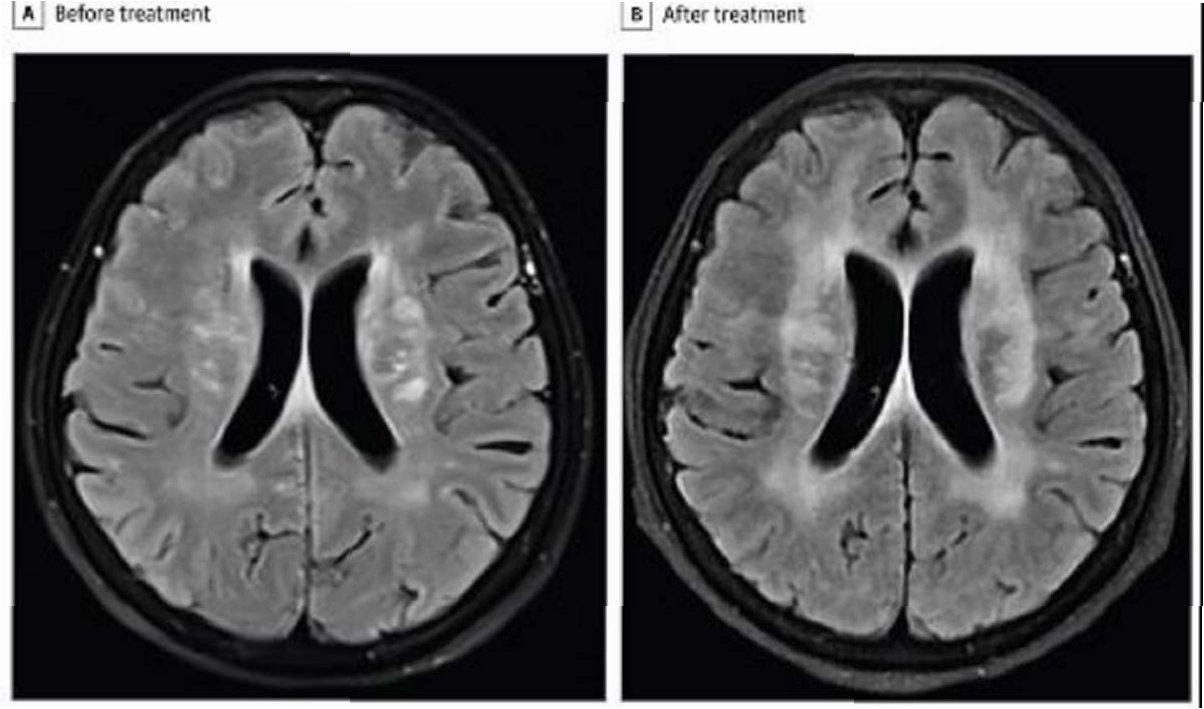

건협은 지난해 7월 발견된 희귀 사례를 공개하며, 60대 여성의 소화불량, 변비, 설사 등의 증상과 대장 내시경 검사에서 발견된 이전고환극구흡충 감염 사례를 상세히 설명했습니다. 이 기생충은 소장 말단과 대장에서 발견되는 것이 특징이며, 2014년 이후 10년 만에 국내에서 발견된 사례입니다. 또한, 20, 30대 유튜버가 아프리카 말라위 호수에서 수영 후 주혈흡충에 감염되어 소변에 피가 나오고 복통과 고열에 시달린 사례는 해외여행 시의 위험성을 경고합니다.

기생충 감염 시에는 복통, 설사, 발열, 소변에 피가 섞여 나오는 증상 등이 나타날 수 있습니다. 이러한 증상이 나타나면 즉시 병원을 방문하여 정확한 진단을 받고, 적절한 치료를 받아야 합니다. 특히, 해외여행 후 이러한 증상이 나타난다면, 여행 국가와 관련된 기생충 감염 가능성을 의료진에게 알려야 합니다. 프라지칸텔과 같은 약물 치료를 통해 완치될 수 있습니다.